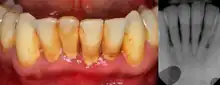

| Gingival enlargement can be a feature in some periodontal diseases. | |

Dental plaque is a microbial biofilm which forms on teeth. This biofilm may calcify and harden, termed calculus (tartar). Plaque tends to build up around the gingival margin (the gumline) and in gingival crevices or periodontal pocket (below the gumline). The release of waste products from the bacteria living in the biofilm causes an inflammatory response in the gums which become red and swollen, bleeding easily when disturbed. This is termed plaque-induced gingivitis and represents the most common form of gingival disease.[5] This inflammatory response in the host can be strongly influenced by many factors such as hormonal fluctuations, drugs, systemic diseases, and malnutrition;[4] which may allow further subdivision of plaque-induced gingivitis (see table).